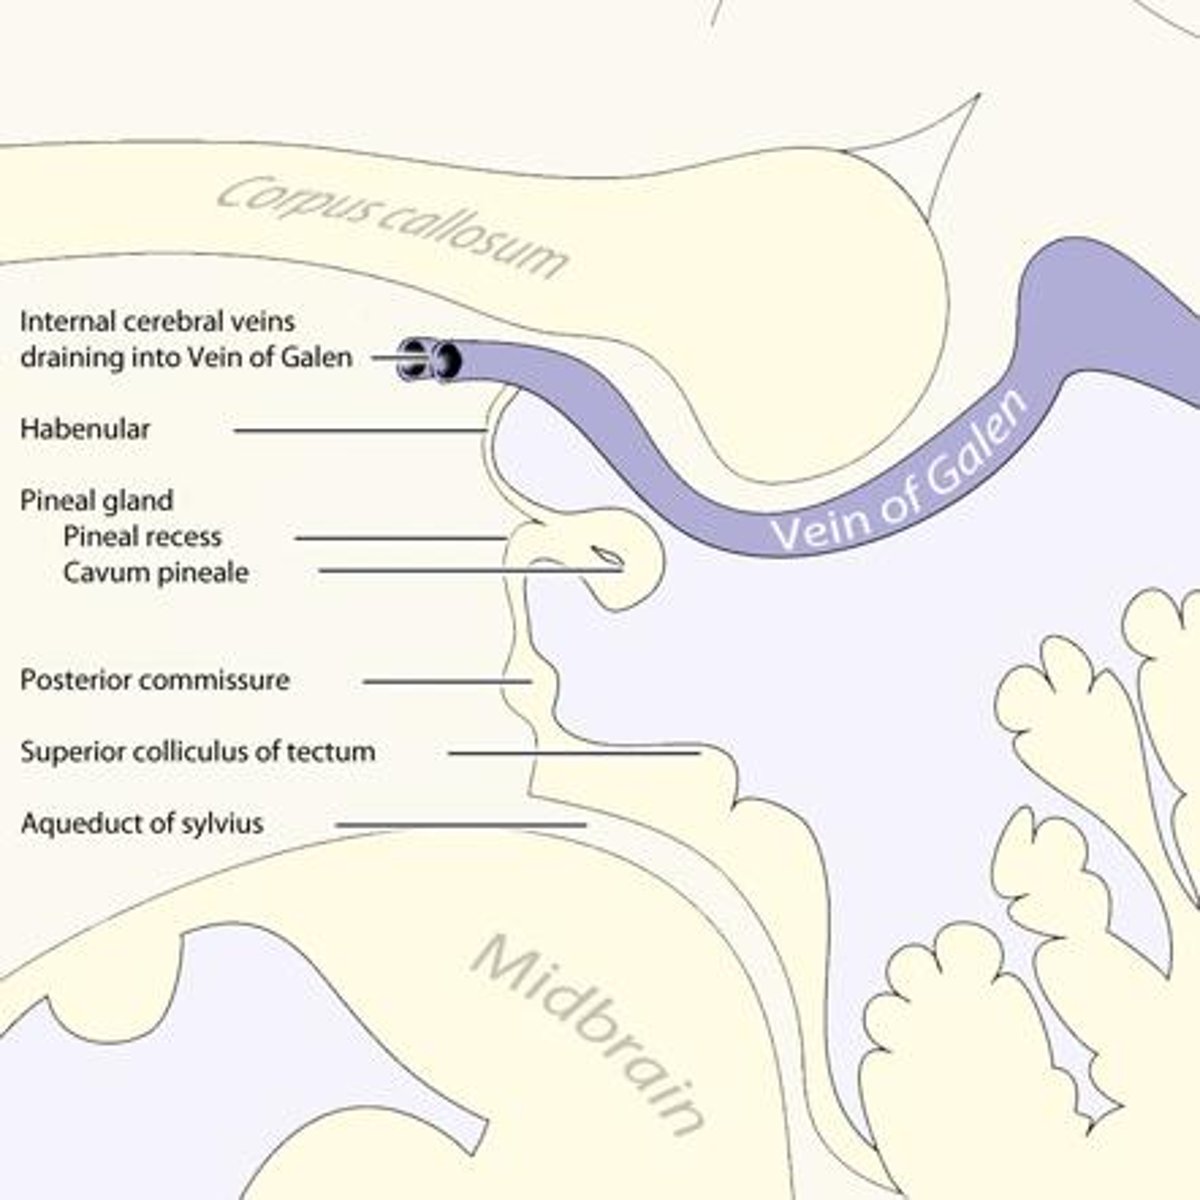

What is the primary nuclei of the epithalamus?

pineal body/gland

What structure is directly inferior to the pineal body of the epithalamus?

posterior commissure

What is the function of the posterior commissure?

largely unknown -- but... pupillary fibers cross here maybe light pupillary response

What is the function of the pineal gland of the epithalamus?

produces melatonin (and responsible for circadian rhythms)

What retinal cells project to the pineal gland, and why?

ipRGCs -- peak sensitivity at 480nm (blue), working on screens can interfere with sleep